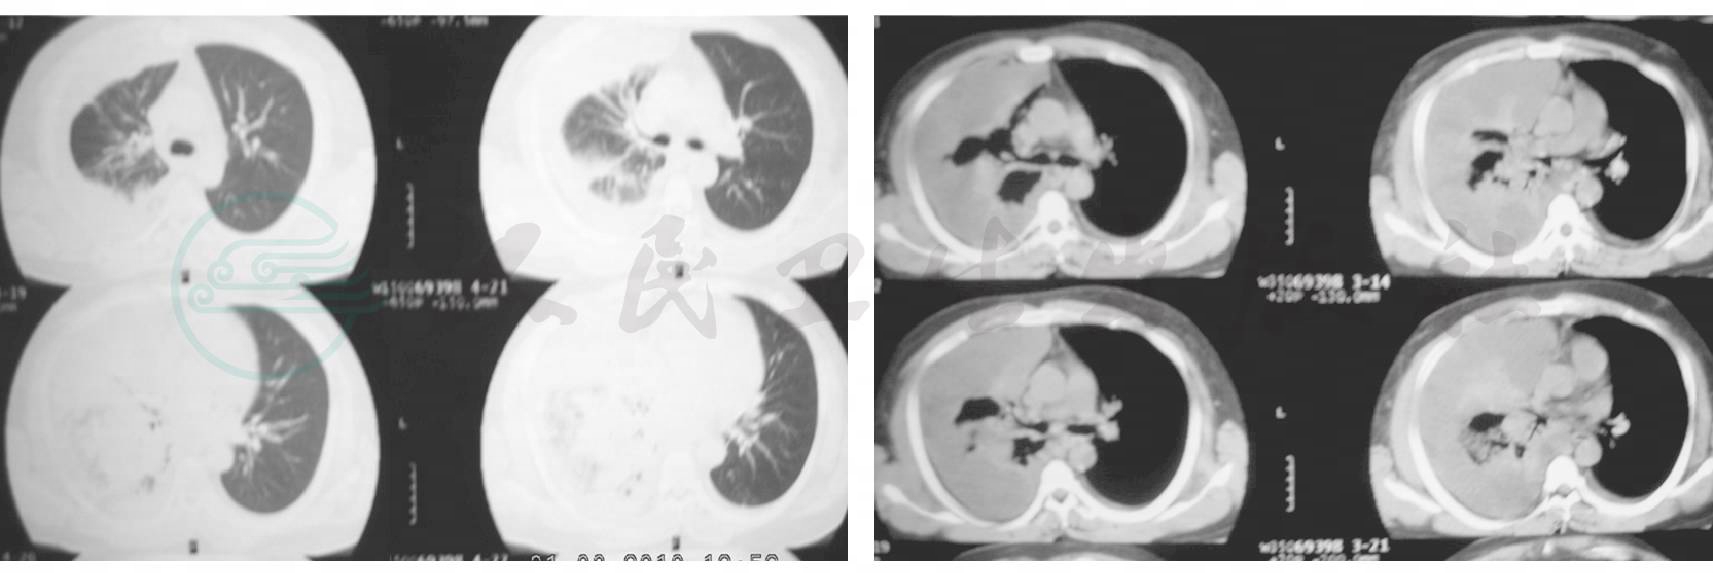

患者,男性,40岁。以发热、咳嗽、咯血、气促9天,双下肢水肿4天为主诉于2009年07月20日入院。患者入院前9天受凉后出现咳嗽,咳少许黄脓痰,痰易咳出,无臭味,咳嗽呈刺激性,伴寒战、发热,体温最高达39.5℃,发热以午后明显,发热时偶有头痛,无抽搐,无腹痛、腹泻、关节疼痛。病初曾咯血约100ml,伴胸闷、气促,活动后为甚,夜间不能平卧,无夜间阵发性呼吸困难。外院胸CT(7月11日):右下肺见团块状阴影(图1),当地医院给予阿奇霉素、头孢哌酮抗感染并予止血、对症等治疗后热退,咯血量减少,咳嗽、气促稍有减轻,4天前出现双下肢水肿,并再次发热,体温高达39℃,仍咯血,每天咯血量约20ml,咳嗽、胸闷、气促明显。复查胸CT(7月16日)示右下肺见团块状阴影增大,出现胸腔积液(图2)。自患病以来睡眠欠佳,无消瘦、乏力、食欲减退现象。

图1 2009-7-11外院胸部CT:右下肺见团块状阴影

图2 2009-7-16外院胸部CT:右下肺见团块状阴影增大,出现胸腔积液

住院经过:入院后予左氧氟沙星0.5g每日1次、头孢吡肟2.0g每日2次抗感染,以及胰岛素降糖、补充清蛋白、解痉、吸氧等治疗。即行右胸腔穿刺术,引流出约200ml茶红色胸腔积液,较混浊。胸腔积液常规提示细胞数21 000×109/L,李凡他阳性,比重1.019,蛋白37.2g/L,LDH 3988U/L,ADA 50U/L。胸腔积液培养报告白假丝酵母菌。7月23日行电子气管镜检查,镜下诊断:右下支气管外压性狭窄。镜检后哮喘急性发作,双肺出现干湿啰音,支气管舒张试验阳性,用药后FEV1占预计53%,此后加入沙美特罗替卡松吸入治疗。7月24胸部CT(图4)示病灶较前稍有吸收。患者发热峰值有所降低,气促较前改善,氧合改善。7月25日再次行右胸腔穿刺抽出胸脓液,脓液培养报告白假丝酵母菌。

图4 2009-7-24胸部CT:病灶右肺病灶较前稍有吸收,胸腔积液较前减少